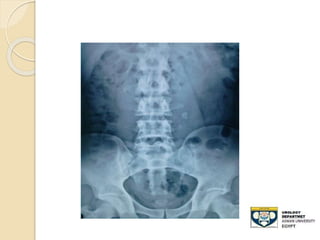

STONE LOWER THIRD URETER